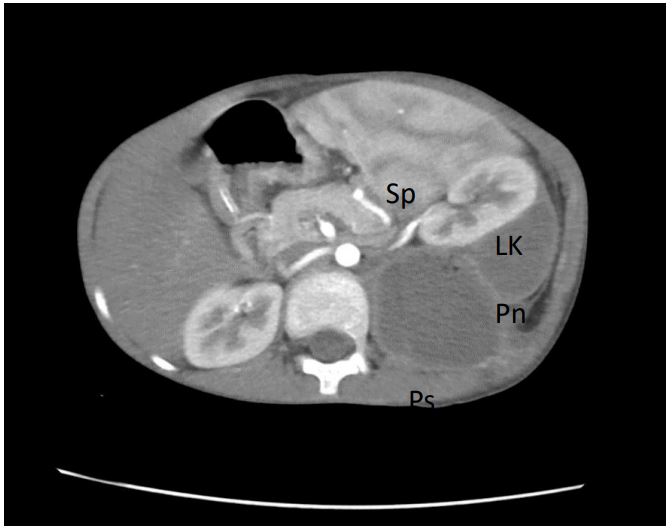

Figure 7: Contrast-enhanced CT showing close relationship between perinephric (Pn) and psoas (Ps) abscesses and anterior displacement of the left kidney (LK) and spleen (Sp).

A renal origin, due to its close proximity to the psoas muscle, can likewise cause direct spread of renal or perirenal infections through the perirenal space although less likely and uncommon (Figure 7) [3,4]. The abundant blood supply of the muscle is believed to predispose it to hematogenous spread from occult sites of infection [3]. With no skeletal involvement observed in our case, a renal origin through a co-existing perinephric abscess is believed to be the primary site of infection.